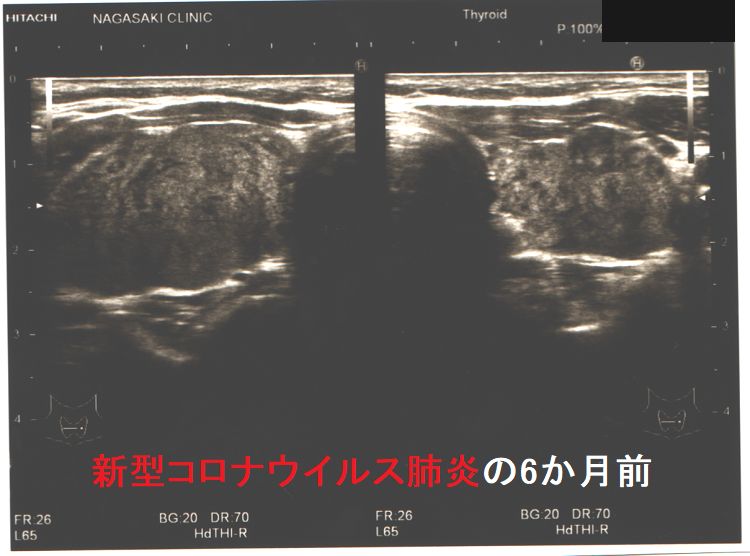

下の写真は、新型コロナウイルス肺炎に罹った甲状腺機能正常橋本病患者の感染前後計12か月の超音波(エコー)画像です。新型コロナウイルス肺炎になる6か月前と6カ月後に、1年に1回の定期検査で長崎甲状腺クリニック(大阪)を訪れていました。新型コロナウイルス肺炎発症時の甲状腺機能は不明ですが、少なくとも6カ月後は正常でした。しかし、発症前に比べて甲状腺は腫大し、腹側(写真下部)の低エコー領域(黒い部分)が拡大しており、橋本病の炎症が増悪したと推察されます。新型コロナウイルス肺炎発症時には破壊性甲状腺炎(無痛性甲状腺炎)を起こしていても不思議ではありません。